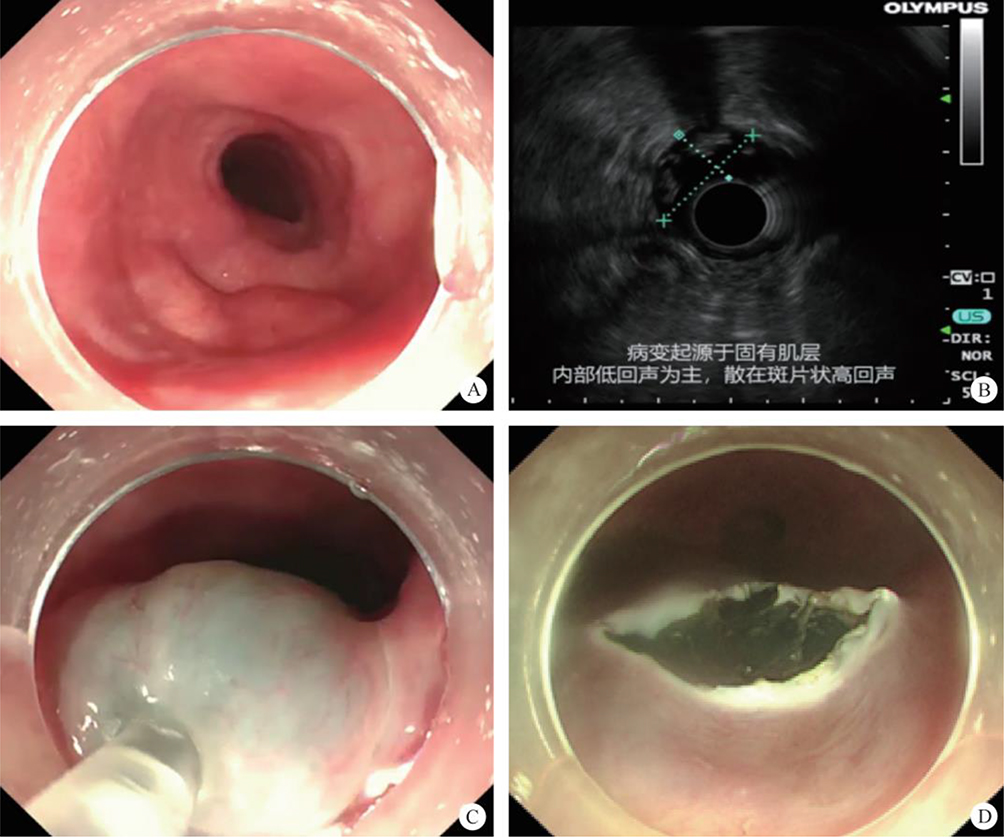

This refers to the operation that meets the super minimally invasive requirements by entering the lacunar or lumen through the puncture route. For instance, laparoscopic, thoracoscopic, arthroscopic-aided operations, related operations after body surface guided puncture bile duct, gallbladder, related operations conducted after ultrasonic endoscopic guided puncture chambers, etc. (figure 2.3).

FIG. 2.3 — SMIS through a puncture channel.